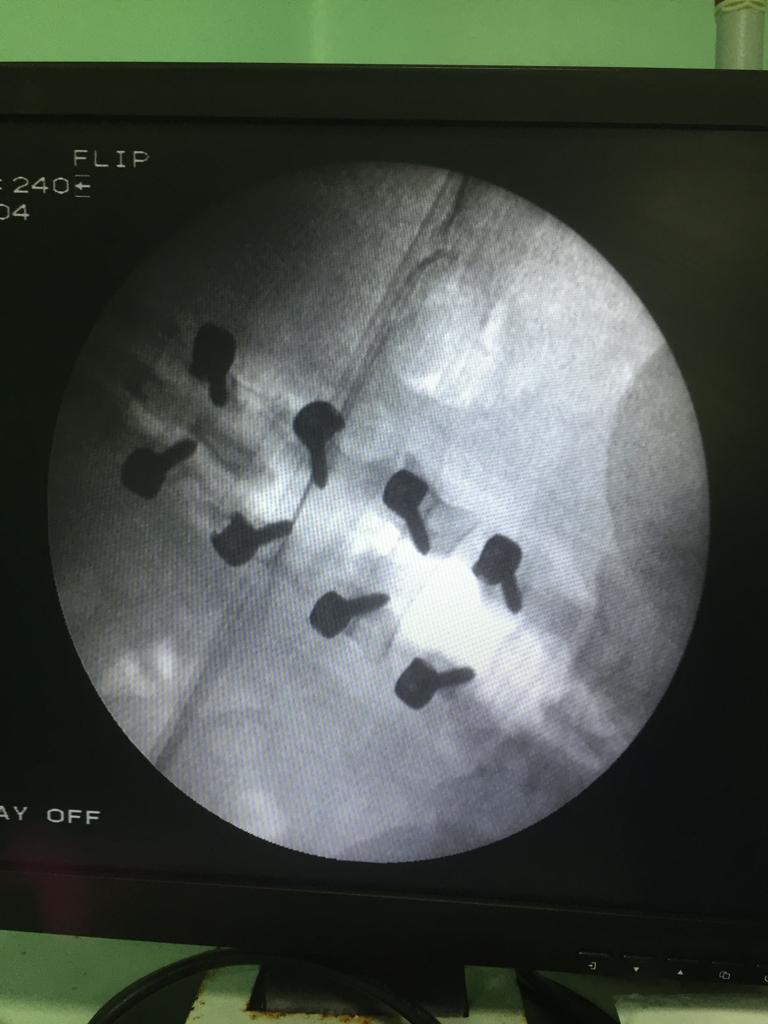

Cases